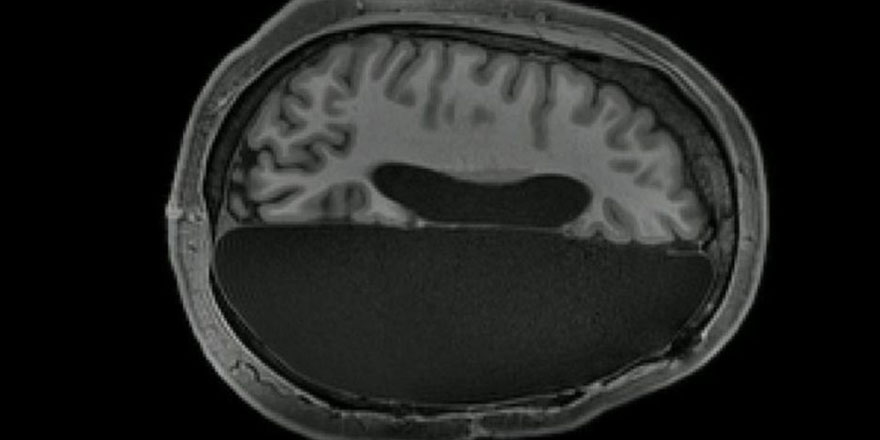

Habere göre bilim insanları, çocukluklarında normal ilaçlarla tedavi edilemeyen şiddetli epilepsi geçiren ve kurtarılmaları için beyinlerinin yarısı alınan 6 hastanın manyetik rezonans tomografisini (MR) çekti.

Ardından araştırmacılar, hasta kişilerin MR sonuçlarını sağlıklı insanlara çekilmiş olan tomografi sonuçları ile karşılaştırdı.

Çalışmanın sonuçları, bir yarım küresi eksik olan insanlarda beynin aktivitesinin, tüm beynin aktivitesi ile büyük bir benzerlik gösterdiğini ortaya koydu.

Bunu kanıtlayan şe ise, tek yarım küredeki nöron ağlarının arasındaki istikrarlı bağlar oldu. Söz konusu bağların tek yarım kürenin eksikliğini kısmen telafi ettiği ve hastanın bilişsel yeteneklerini desteklediği ortaya çıktı.